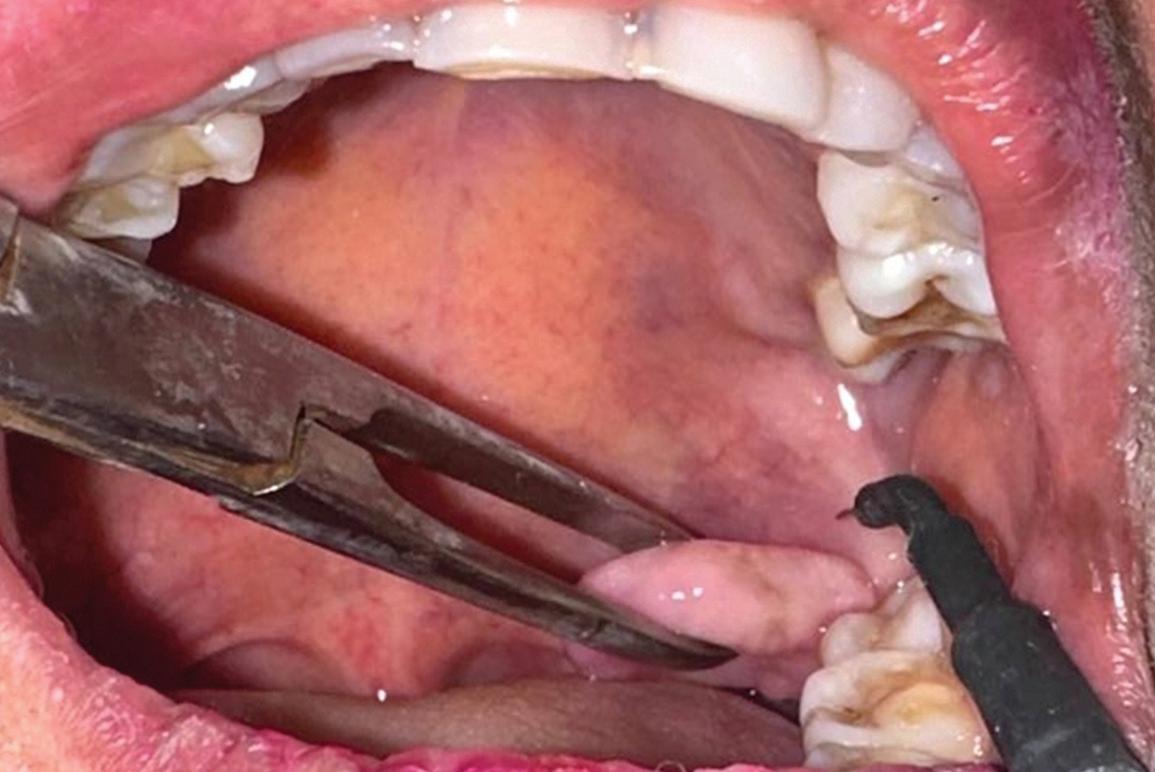

The flap design for implant cases usually extends to half a tooth beyond the surgical site in each direction. For example, for an implant at site 19, the flap is extended to the mesiofacial surfaces of teeth 18 and 20. It is also reflected at least 2 mm buccally and lingually to allow full visualization of the bone at the surgical site. The flap is raised with a Woodson elevator or a Molt No. 9 elevator, and the surgical site is examined (Fig 5). The surgical guide is tried on to ensure there are no issues with the fit or positioning of the guide (Fig 6). One benefit of using a surgical guide is that it holds the flap out of the way once it is

Fig 5. The reflected flap reveals bleeding vital bone and maintenance of ridge width.